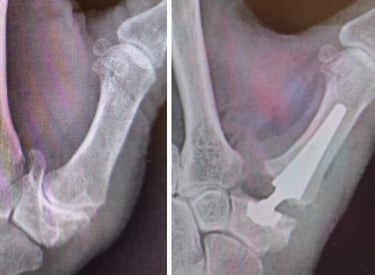

Articulación muy susceptible a algunas enfermedades como la artrosis, las fracturas de radio y cubito o las lesiones de los ligamentos.

Artroscopia de muñeca

Cirugía mínimamente invasiva para la patología más compleja de la muñeca